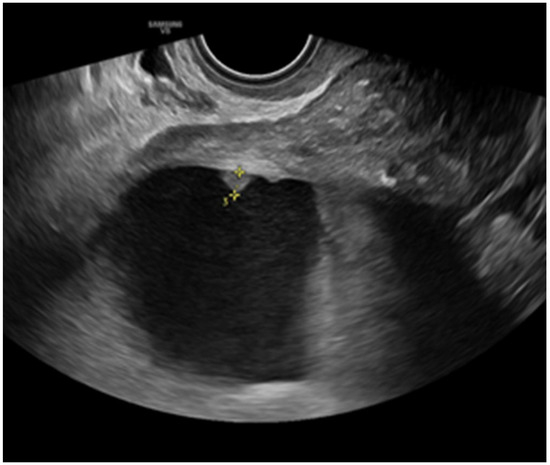

Background: Ovarian cancer is one of the most lethal gynecological malignancies, often diagnosed at an advanced stage. The prognosis is generally poor, with high recurrence rates and limited long-term survival. Understanding the genetic and molecular...